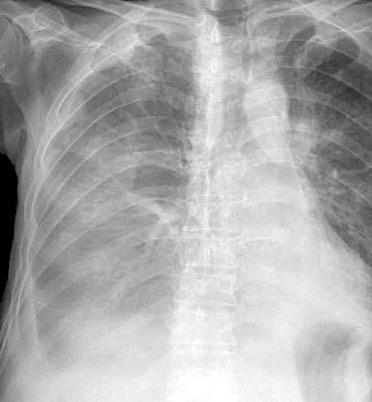

Neumonía a neumococos base izda. con derrame que aumenta.

Broncograma en lateral y en US.

(36-66% en ingresados)